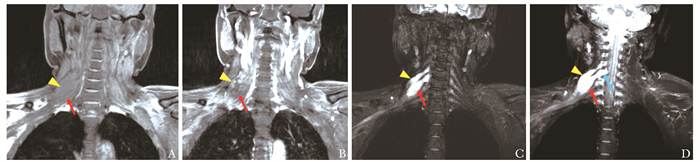

臂丛神经淀粉样变性一例

孙翀, 林洁, 郑永胜, 刘炳佑, 陈琳, 鲍奕仿, 赵重波

2022, 1(2): 178-182. DOI: 10.12376/j.issn.2097-0501.2022.02.011

摘要 HTML全文 PDF